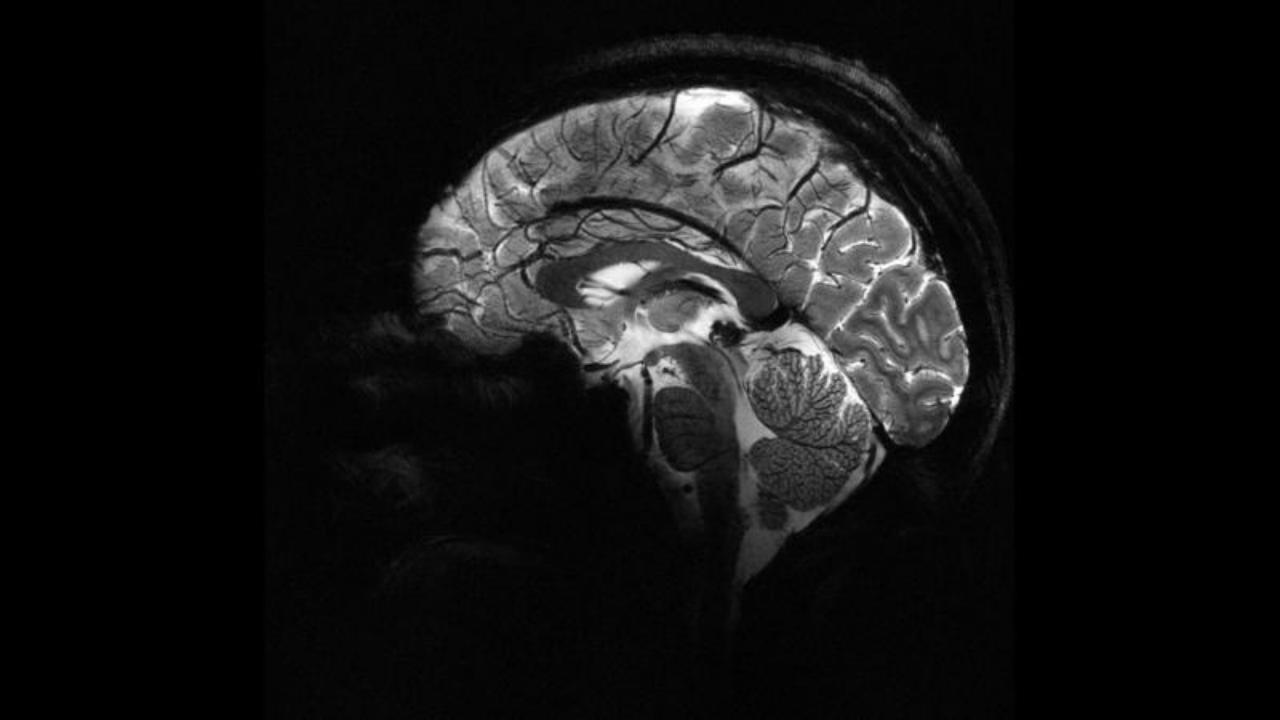

Yapay zeka, epilepsili çocuklarda doktorların gözden kaçırdığı gizli lezyonları buldu

Avustralyalı araştırmacılar, epilepsi hastası çocuklarda doktorların gözden kaçırdığı çok küçük beyin malformasyonlarını tespit edebilen bir yapay zekâ aracı geliştirdi. Uzmanlar, bu sistemin çocukların hayatlarını değiştirebilecek cerrahi operasyonlara daha hızlı erişmesine imkân sağlayabileceğini belirtti.